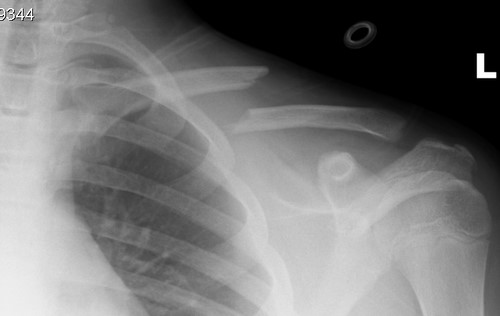

Spent the morning in Kingston Hospital with older son. Last Saturday he broke his collarbone playing rugby, down in Somerset at school. So he’s been home all week, and this morning I took him in for his fracture clinic appointment. In typical fashion we weren’t seen until an hour after our appointment time, and they couldn’t locate his X-ray, so he had to have another (above). It shows that there’s a bit of a problem: that clavicle is well and truly broken. They are going to see whether the bone knits back together; otherwise an operation may be in order.